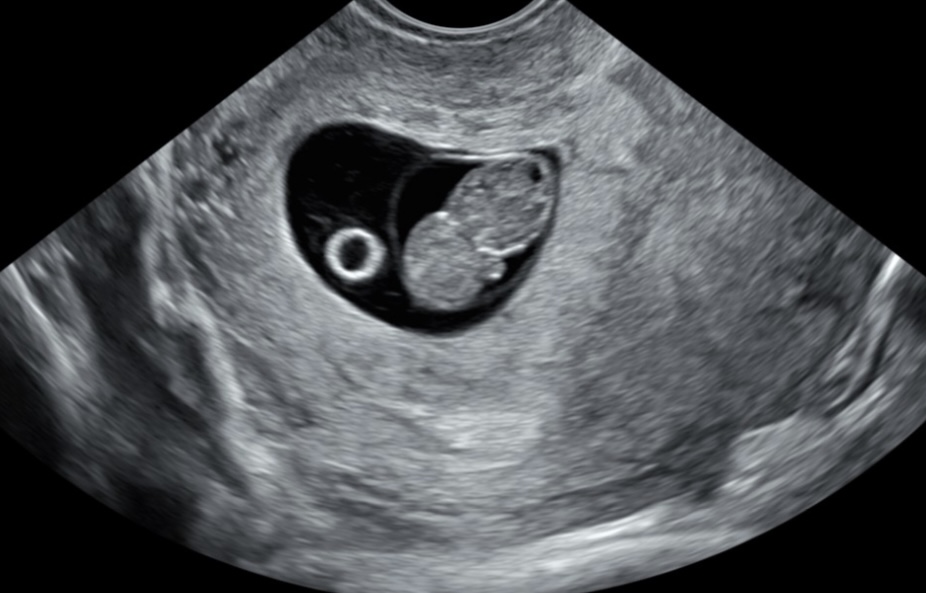

משו מוזר לי באולטרסאונד 😅 אולי מישי תדעאנונימית בהו"ל

אבל מה זה העיגול הזה לידו?😂😂

מץמונות סתם שגאיתי בגוגל זה נראה כמו שק חלמון אבל זה לא יכול להיות שק חלמון…

שק חלמון למיטב ידיעתיאנונימית בהו"ל

ככה נראה שק חלמוןYaelL

אין לזה שלבים. זה פשוט עיגול קטן. זה לא שק הריון.

זה מבנה שנמצא בנוסף לעובר. לא נוצר מזה עובר.

כשיש עובר בהכרח יש גם שק חלמון

ככה נראה א''ס בשלבים האלה עד שמתפתחת שילייה

זה שק חלמוןYaelL

למה לא יכול להיות? זה משהו שאמור להיות, למה שזה יצויין במיוחד? מה שחשוב זה שיש דופק. זה כן אמור להיות רשום בתאור של האולטרסאונד, אבל לא מחייב שהרופאה/טכנאית יציינו את זה כי זה לא פרט משמעותי. כמו שלא מציינים בשבועות מתקדמים יותר שיש שלייה, ברור שיש שלייה, אחרת לא היה עובר והריון.